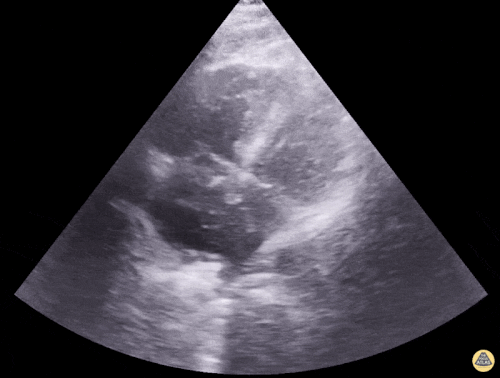

4

Based on the ultrasound image below, which shock etiologies are least consistent with this finding?

1 pts